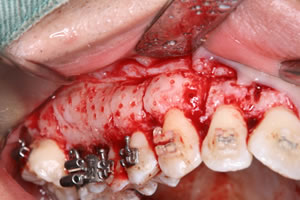

PAOO(歯周外科処置)術中写真:上顎

歯ぐきを切開した後、歯を支える骨が厚くあるため、骨の表面に小さく傷をつけて活性化させます。